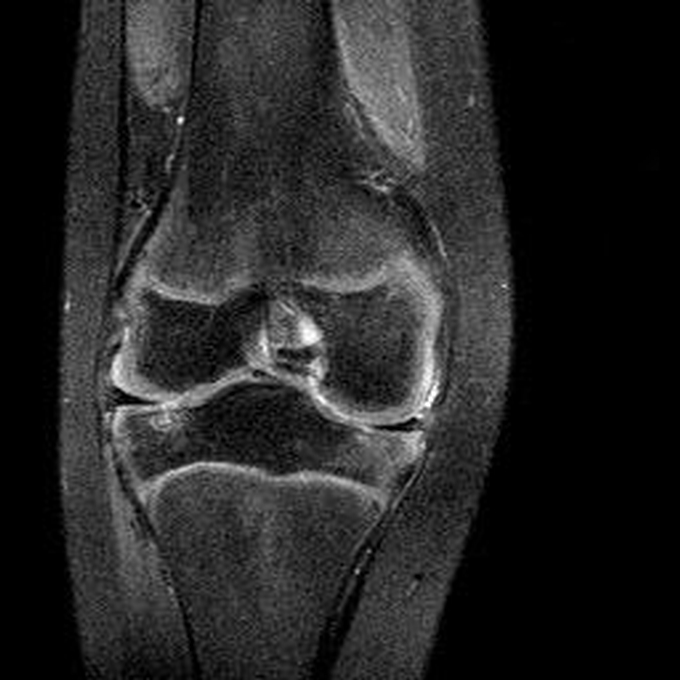

Haemophiliearthropathie bei Haemophilie A.

ARC123 Haemophiliearthropathie bei Haemophilie A.